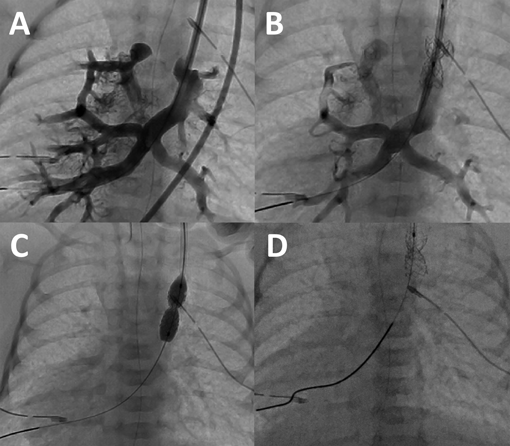

総肺静脈還流異常を合併した垂直静脈狭窄に対するステント留置中のバルーンエントラップメントEntrapment of a Balloon Catheter during Stent Implantation for Vertical Venous Stenosis in Two Neonates with Single Ventricle and Total Anomalous Pulmonary Venous Connection